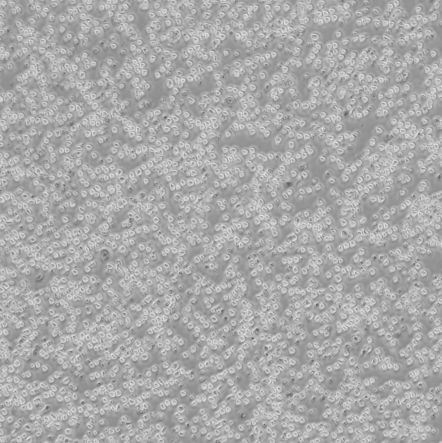

细胞名称:OPM-2_人骨髓瘤细胞

细胞形态:圆形细胞

细胞规格:1 X 106cells/T25或1 mL冻存管

培养条件:90% RPMI 1640 + 10% h.i. FBS

37 ℃, 5% CO2